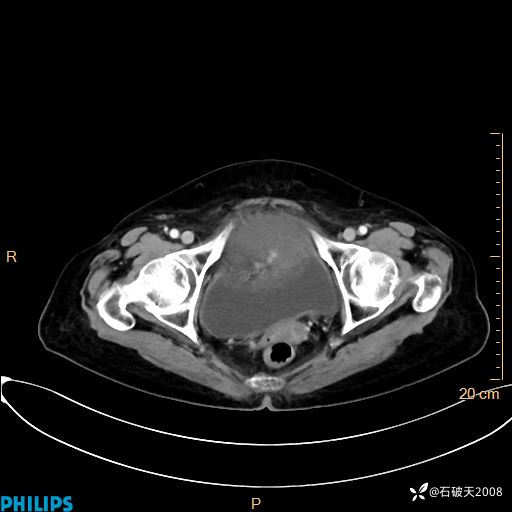

MIP